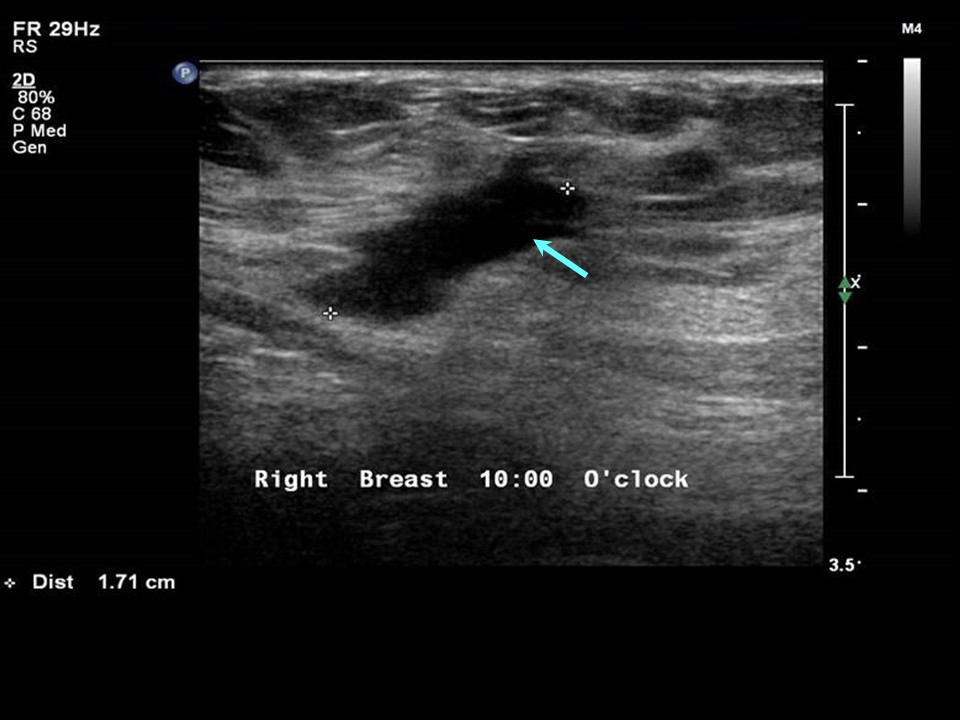

From mbaheblogjpdzpn.blogspot.com

Where is 10 o'clock position on breast 258089Where is 9 o'clock left Breast Ultrasound Clock Face When deciding on the clock face location of a finding on mammography two standard. The location of breast findings on ultrasound are described by both orientation on a clock face and distance from the nipple. Findings in the breasts are described by their orientation on a clock face (figure 1). Breast ultrasound is an important modality in breast imaging. The. Breast Ultrasound Clock Face.